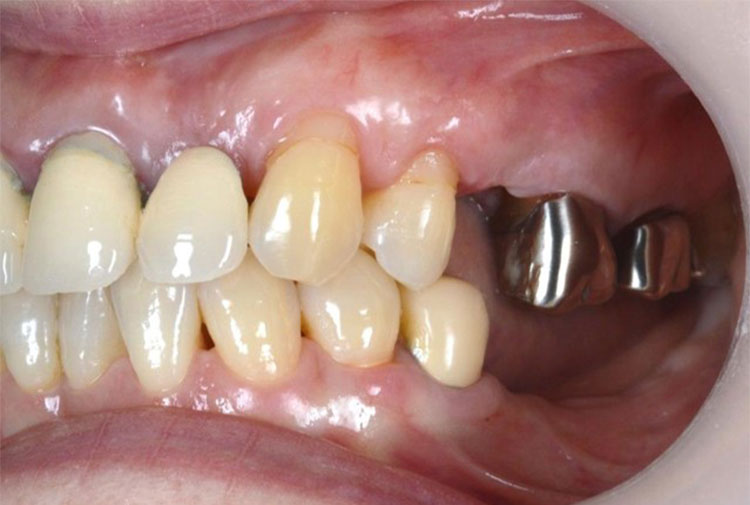

インプラント症例 Case2

Treatment cases

Before

After